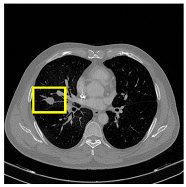

3.4.2. Representative Cases with Segmentation Challenges on the MEF-PN35 Dataset

To complement the quantitative evaluation, we present a set of representative cases from the clinical dataset that exhibited typical segmentation challenges. These cases were selected to reflect diverse morphological characteristics observed in pulmonary nodules, such as spiculated boundaries, small size, vessel adherence, pleural attachment, cavitation, and clear isolation. Rather than aiming for exhaustive categorization, our intent is to highlight a range of practical difficulties encountered in real-world scenarios and to qualitatively assess how different boundary-aware loss functions respond to these variations. Each challenge is labeled (C1) through (C5) in Table 10 and is consistently referenced in the corresponding detailed illustrations that follow.

Following the summary in Table 11, we present detailed visual comparisons for selected representative cases, each corresponding to a specific segmentation challenge. These cases are consistently labeled using the Challenge ID (CID) codes defined in Table 9 to facilitate cross-referencing between the summary and the case illustrations. Each table reports segmentation results across three loss configurations (Sobel, Laplacian, and Hausdorff) using five columns. Loss indicates the boundary loss formulation applied in each case, where Dice loss is combined with a boundary term computed using Sobel, Laplacian, or Hausdorff operators. The Segmentation Result column shows four images side by side: the input CT patch, the manual ground truth, the model prediction, and a color-coded difference map between ground truth and prediction. In this map, green indicates true positives, blue represents true negatives, red corresponds to false positives, and yellow denotes false negatives. The final column, Attention Map, presents Grad-CAM visualizations derived from one of the Adaptive Attention Fusion (AAF) layers in the encoder path. These maps illustrate the spatial focus of the model, with red/yellow regions indicating strong attention and lighter or neutral tones indicating lower activation. All six cases are presented in detail in Table 11, Table 12 and Table 13, providing a comprehensive qualitative analysis of how each loss configuration performs under specific segmentation challenges observed in real clinical data.